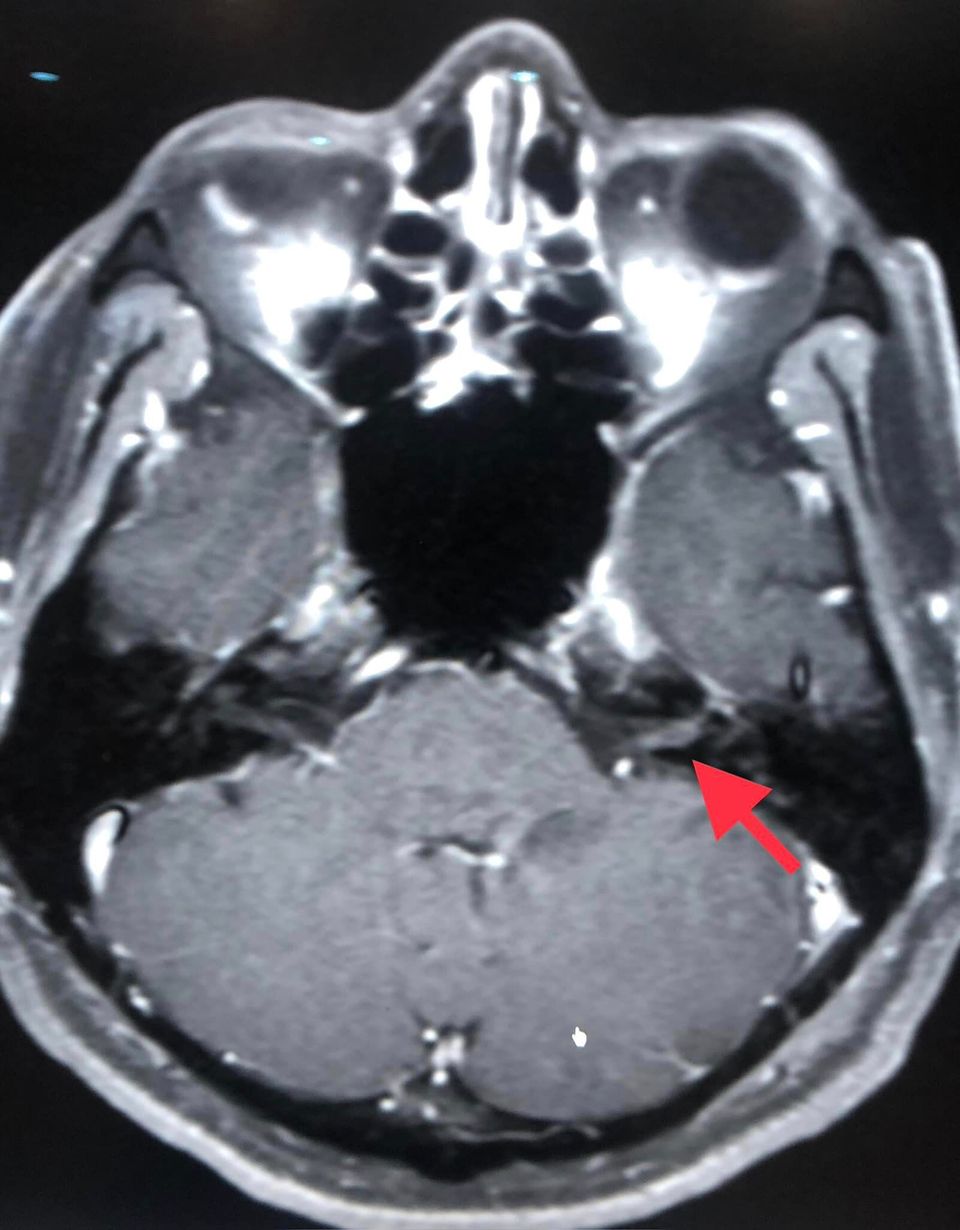

ผลการตรวจคลื่นแม่เหล็กไฟฟ้าสมอง (MRI brain) พบมีการอักเสบของเส้นประสาทในสมองข้างซ้ายเส้นที่ 7 และ 8 เจาะเลือดตรวจแอนติบอดีเฉพาะต่องูสวัด Varicella IgG >5,000 ให้ผลบวก Varicella IgM ให้ผลลบ และเมื่อเจาะหลัง ตรวจน้ำไขสันหลัง พบเม็ดเลือดขาวในน้ำไขสันหลังสูง 188 เชลล์ เป็นชนิดลิมโฟไซต์ (lymphocyte) 100% ค่าโปรตีนสูงเล็กน้อย 58.3 ค่าน้ำตาล ปกติ 76 ส่งตรวจรหัสพันธุกรรม PCR น้ำไขสันหลังพบเชื้อไวรัสงูสวัด (Varicella Zoster Virus )

แพทย์วินิจฉัยว่า ติดเชื้อไวรัสวาริเซลลา (Varicella Zoster Virus: VZV) ไวรัสงูสวัด ซึ่งเป็นไวรัสชนิดเดียวกันกับไวรัสโรคอีสุกอีใส มีอาการแทรกซ้อน เส้นประสาทในสมองข้างซ้ายเส้นที่ 7, 8, 9, 10 อักเสบ และเยื่อหุ้มสมองอักเสบ ให้ยาฆ่าเชื้อไวรัส acyclovir ทางเส้นเลือดนาน 14 วัน และให้ยาเสตียรอยด์ร่วมด้วย